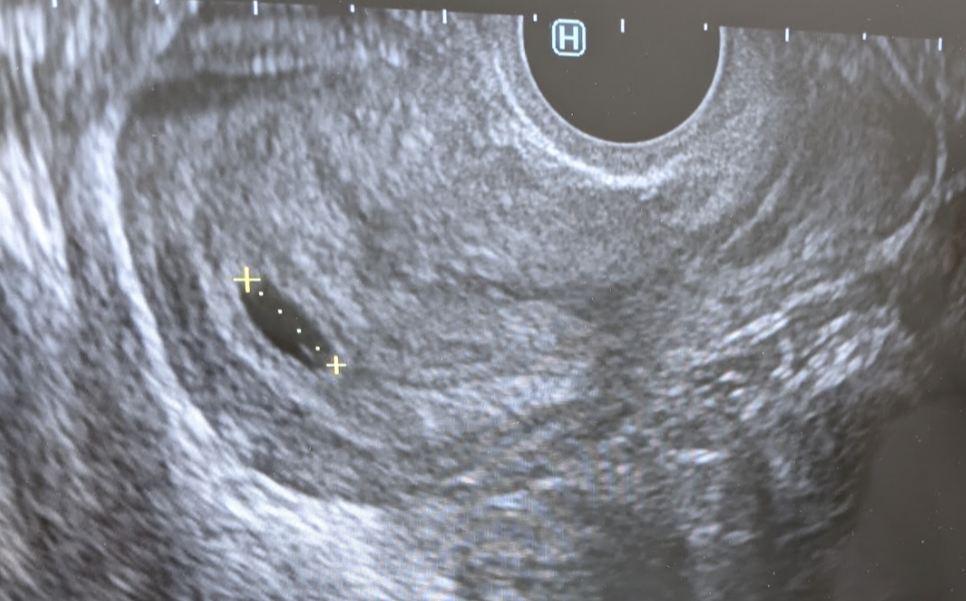

초음파 검사를 하자마자 의사 선생님이 하는 말.

妊娠ですね。これが袋です。

(임신이네요. 이게 아기집이에요.)

너무 조그맣고 소중한 아기의 첫 초음파 사진

임신 5주 차에 그 존재를 알게 된 우리 아기. 당장 한국에 있는 엄마, 아빠에게 전화해서 소식을 알렸다. 결혼 후 늘 손주를 기다려왔던 부모님이었던지라 정말 기뻐했다.